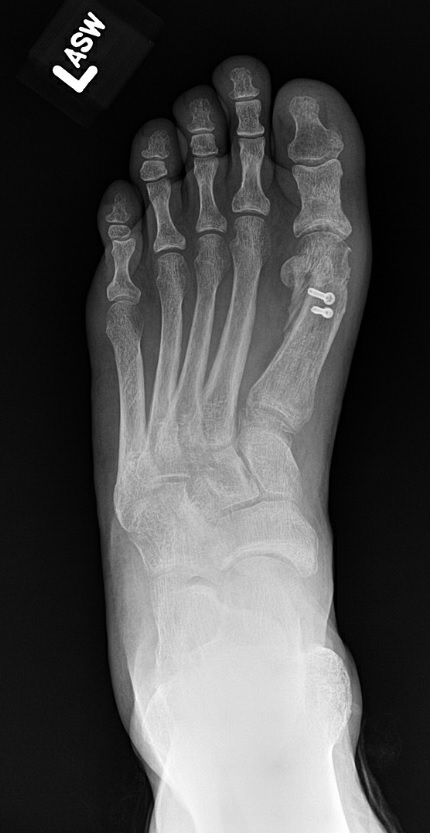

The surgical team places a well-padded soft dressing and surgical shoe to the operative foot and advises non-weight-bearing to the forefoot for four to six weeks postoperatively. At two weeks, sutures removal takes place. Radiographs at two and six weeks postop evaluate for maintenance of deformity correction, bony incorporation of the osteotomies, and viability of fixation. In the specific case presented here, there is demonstration of improved correction compared to the

preoperative films (Fig. 7). At four to six weeks postoperatively, the patient may initiate weight-bearing to the forefoot. After the six-week visit, patient-directed physical therapy begins, and the patient performs passive range of motion exercises of the first metatarsophalangeal joint as directed. At around 8 weeks, patients can wear regular shoes and perform activities as tolerated.